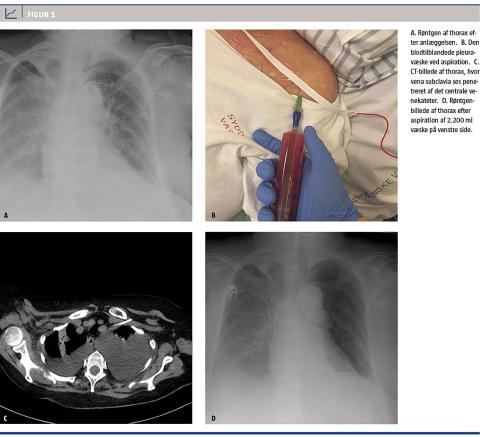

En 71-årig kvinde, der havde kronisk obstruktiv lungesygdom samt dissemineret mammacancer og var i palliativ behandling, blev indlagt på en internmedicinsk afdeling med erysipelas på den ene underekstremitet. Hun blev svært septisk, og pga. vanskeligheder med at anlægge perifere venøse adgange fandt man indikation til anlæggelse af et CVK. Dette blev gjort infraklavikulært i venstre vena subclavia. I forbindelse med anlæggelsen, der var uproblematisk, kontrollerede man, at der var frit frem- og tilbageløb af blod i kateteret. Efter anlæggelsen tog man et røntgenbillede af thorax (Figur 1), hvor den anlæggende anæstesiolog ikke så pneumothorax. Dagen efter bemærkedes det ved vurdering af en radiolog, at kateteret ikke lå i vena cava superior, men muligvis i venstre vena mammaria. I øvrigt var der diskrete pleurale ansamlinger og infiltrater bilateralt. CVK‘et blev taget i brug. Man skønnede, at patienten ville have behov for en længere indlæggelse, hvorfor hun blev overflyttet til sygehusets onkologiske afdeling, hvor man kunne varetage behandlingen af infektionen samtidig med den palliative behandling. Hendes tilstand rettede sig kun langsomt klinisk og paraklinisk. På fjerde indlæggelsesdøgn klagede hun over smerter i venstre side af brystet, samtidig med at hun havde udtalt dyspnø, takypnø og desaturerede til 80%, på trods af at hun lå med 15 l ilt på maske. Symptomerne sammenholdt med udbredte krepitationer ved lungestetoskopi gav mistanke om kardiogent lungeødem, og man ordinerede intravenøst givet furosemid. Inden indgift i CVK‘et aspirerede man, og det blev bemærket, at den aspirerede væske ikke var rent blod, omend den var rødlig. Yderligere aspiration af 300 ml var tilsvarende »tyndt blodig«. Patienten fik foretaget en CT af thorax, hvorved man afslørede, at spidsen af CVK‘et var beliggende frit i pleurahulen. Desuden vurderede man, at der stod minimum 1.000 ml fri væske i pleurahulen. Man aspirerede herefter 2.200 ml væske, og i forbindelse hermed bedredes patienten fuldstændigt respiratorisk. Man satte en pleuracentesepose til CVK‘et og lod det ligge til dagen efter uden videre produktion af væske, hvorefter det seponeredes helt ukompliceret, og man anlagde et nyt CVK via højre vena jugularis interna.